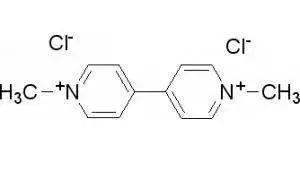

百草枯,又名克无踪,化学名称1-1-二甲基-4-4-联吡啶阳离子盐,化学式是(C12H14N2)2+。